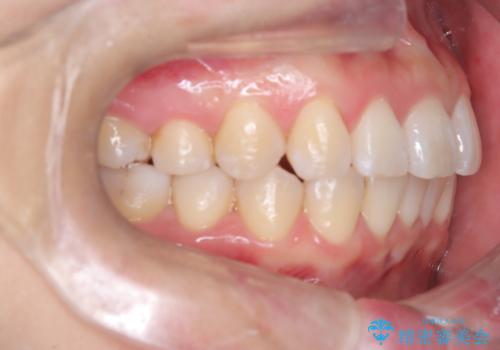

- 「歯のガタつきが気になる」「前歯の真ん中がずれている」との主訴で来院されました。診察の結果、上下の歯列に中等度の叢生(凸凹)があり、特に前歯の位置のずれ(正中の偏位)が目立つ状態でした。見た目だけでなく、かみ合わせにも影響を与える可能性があるため、全体的なバランスの改善が必要と診断しました。

治療はインビザラインを使用し、1~2週間ごとに新しいマウスピースに交換しながら段階的に歯を移動させていきました。特に上下の正中が揃うよう、奥歯や前歯の位置関係に注意を払いながら細かく設計を調整。途中の確認でも、左右のバランスが取れてきたことをご本人も実感されていました。

治療期間は約1年半で、ガタついていた歯列はきれいに整い、上下の前歯の真ん中もぴったりと揃えることができました。透明なマウスピースのため周囲に気づかれず治療が進み、快適に続けられたとの感想もいただいています。